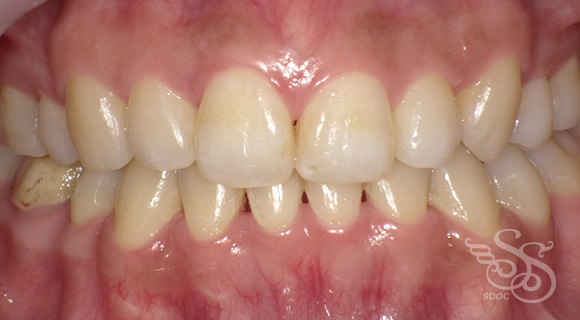

久しぶりに会った友人に「整形した?」と言われた患者さま

術前

術後